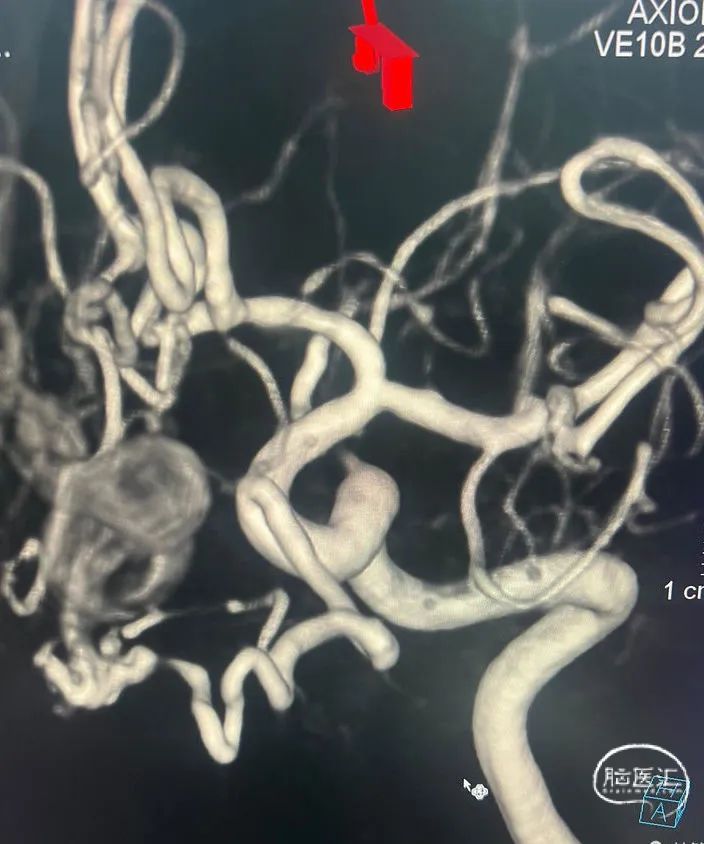

术前影像资料

术前3d

左侧比较粗,先解决主要矛盾,或许可以通过一根血管搞定。